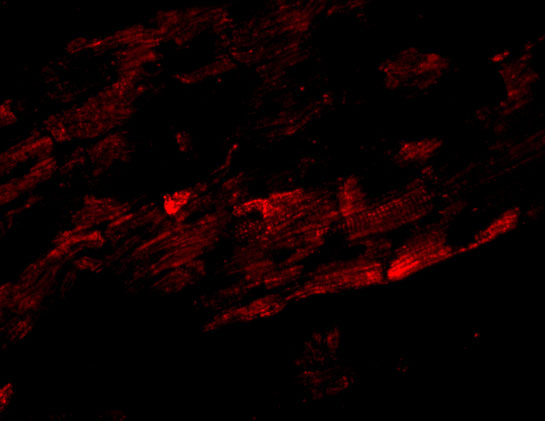

Cytoplasm, cytoskeleton, microtubule organizing center, centrosome. Midbody. Localizes to the centrosome during all stages of the cell cycle. Recruited to the midbody during cytokinesis by KIF13A.